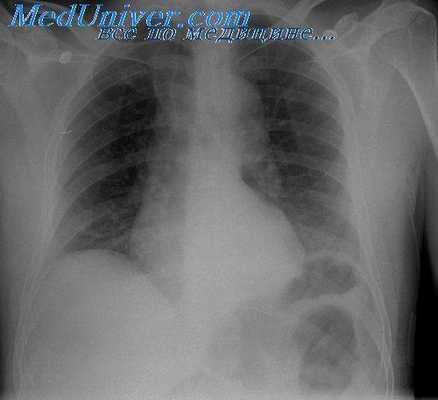

При портальной гипертензии наблюдается варикозное расширение вен пищевода и желудка, которое может осложниться кровотечением. Для оценки локализации и степени выраженности варикозного расширения вен применяют рентгенологическое исследование пищевода и желудка с суль-